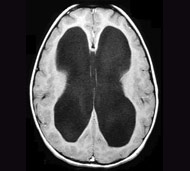

Гідроцефалія виникає при скупченні надлишкової кількості рідини в головному мозку, в більшості випадків внаслідок обструкції (закупорки), що порушує нормальне дренування рідини. Надлишкова рідина може притиснути тендітні тканини головного мозку до черепа, викликаючи ураження головного мозку і, якщо не розпочато лікування, навіть смерть.

Консистенція головного мозку нагадує желе, яке, наче, плаває в черепі, наповненому спинномозковою рідиною. Ця рідина також заповнює великі порожнисті структури, які називаються шлуночками і які розташовані в глибині головного мозку.

Спинномозкова рідина проходить через шлуночки, що є системою сполучених посудин та каналів. Потім рідина потрапляє в закриті простори, розташовані між головним мозком і черепом, де вона поглинається кровотоком.

Збалансовані утворення, циркуляція і поглинання спинномозкової рідини мають важливе значення для підтримання нормального тиску в черепі. Гідроцефалія розвивається тоді, коли відтік спинномозкової рідини порушений, наприклад, при звуженому каналі між шлуночками або при порушенні абсорбції рідини організмом.

Порушення абсорбції спинномозкової рідини викликає розвиток нормотензивної гідроцефалії, що найчастіше спостерігається у літніх людей. При нормотензивній гідроцефалії надлишкова рідина розширює шлуночки, але не підвищує тиск, який впливає на головний мозок. Нормотензивна гідроцефалія може виникнути внаслідок травми або захворювання, але в більшості випадків причини її виникнення невідомі.

Огляд дитини або дорослої людини, у яких розвиваються ознаки або симптоми гідроцефалії, починається з ретельного збору анамнезу, фізикального і неврологічного обстеження. Комп'ютерна томографія (КТ) або магнітно-резонансна томографія (МРТ) можуть надати детальні зображення головного мозку. Якщо на цих зображеннях виявляється гідроцефалія або інша патологія, ймовірно, вам видадуть направлення на консультацію до нейрохірурга для подальшого обстеження.